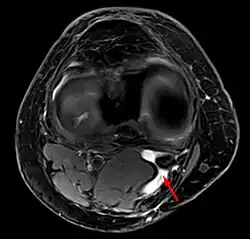

Baker's cyst on axial MRI with communicating channel between the semimembranosus muscle and the medial head of the gastrocnemius muscle. -